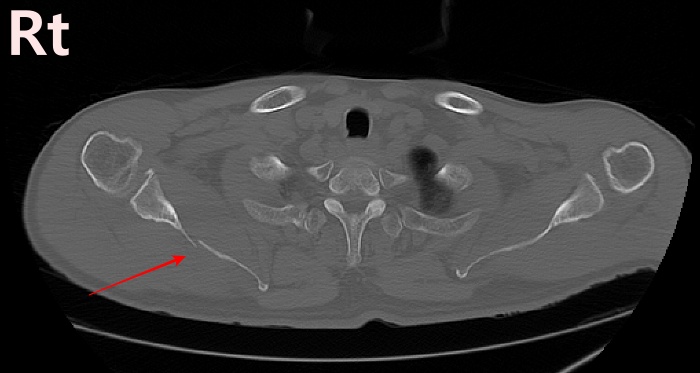

2022.06.07 CT SCAN

- M/50대

- fall down

- X-Ray 검사 상 견갑골 골절의심 됨

- Axial Scan 후 MPR로 Axial, Coronal, Sagittal image Recon 함

- Rib CT 포함하여 검사함.

mildly displaced fracture of body of scapula.